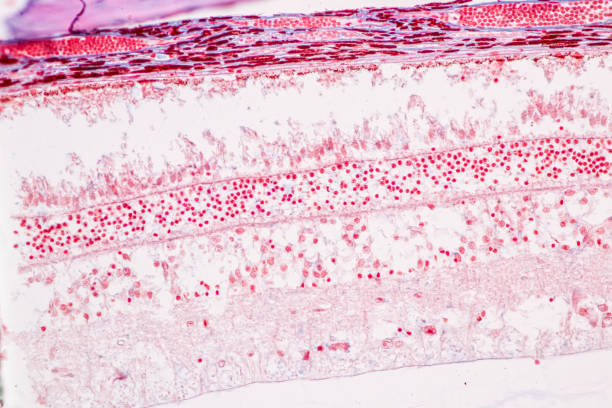

대표적으로 녹내장의 원인은 안압상승으로 인해 시신경이 손상원인이 녹내장 질환을 발생하게 합니다. 나이가 들면 노화가 진행됨으로써 눈의 각 부분 조절능력이 떨어져 안구 내의 안압이 높아지면서 이로 인해 뇌로 연결되는 시신경이 손상되면서 녹내장이 발생됩니다. 녹내장이 나타나면 시야가 좁아지면서 심하면 실명할수도 있습니다. 녹내장을 유발하는 대표적인 원인에 대해 알아보겠습니다.

녹내장 초기증상 두 번째는 시력 저하입니다. 녹내장은 일반적으로 무증상이지만 점진적인 시력 저하가 특징입니다. 어느 날 물체가 흐릿하게 보이거나 시력이 상실된 것을 발견하면 녹내장을 의심할 수 있습니다.

녹내장은 안통과 두통뿐 아니라, 시신경 손상으로 인한 안구 충혈을 유발할 수 있습니다. 만일, 이러한 안구 충혈이 지속해서 발생하는 경우 녹내장을 의심해볼 수 있습니다.